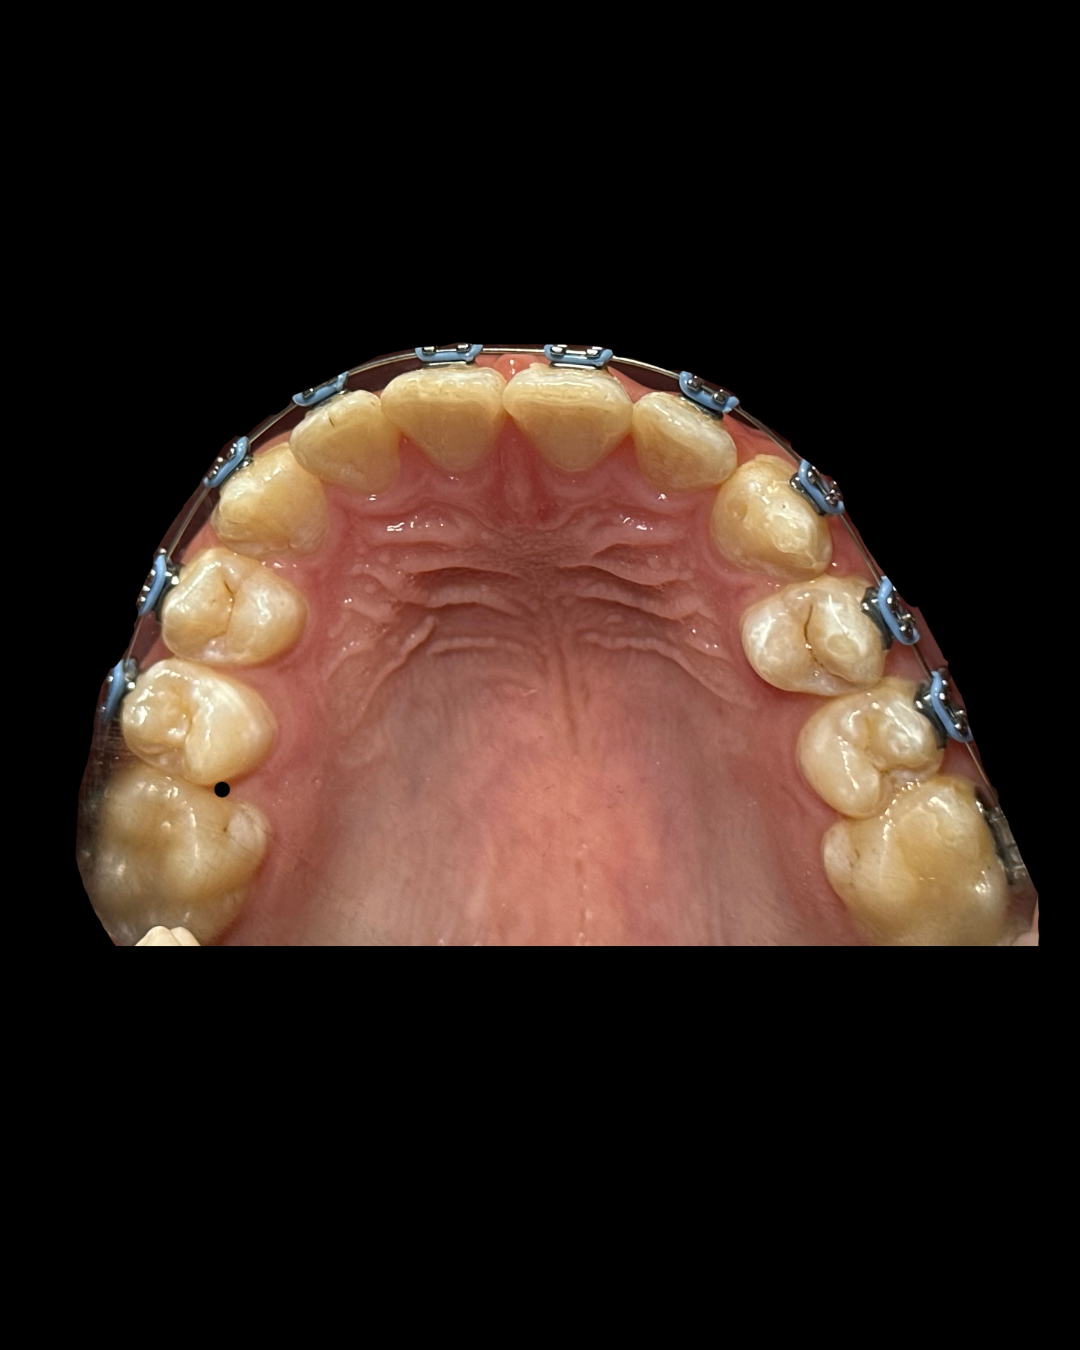

Алиева Арзу Намазовна

Придерживается принципов функциональной стоматологии и индивидуального подхода, чтобы каждая улыбка была не только красивой, но и здоровой.

4 года